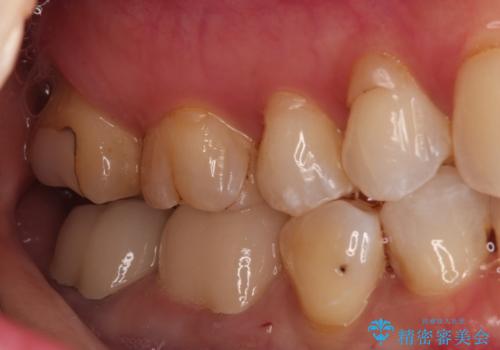

- 他院で治療した被せ物が取れたを主訴に来院された患者様です。被せものが外れた隣の歯もプラスチックの詰め物の劣化や歯に亀裂があったためオールセラミッククランで治療を行いました。

- 242,000円(仮歯11,000円×2本、オールセラミッククラウンスタンダード110,000×2本)費用は治療当時の料金となります

昔詰めたプラスチックの詰め物の範囲が大きいのと破折のリスクや強度の担保のためインレーではなくクラウンで治療を行いました。